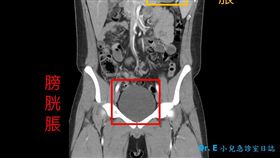

30歲男吃飯突胃穿孔開刀!竟是這傳言導致

外科醫師陳榮堅在臉書發文分享,一名30歲男子肚子痛,...